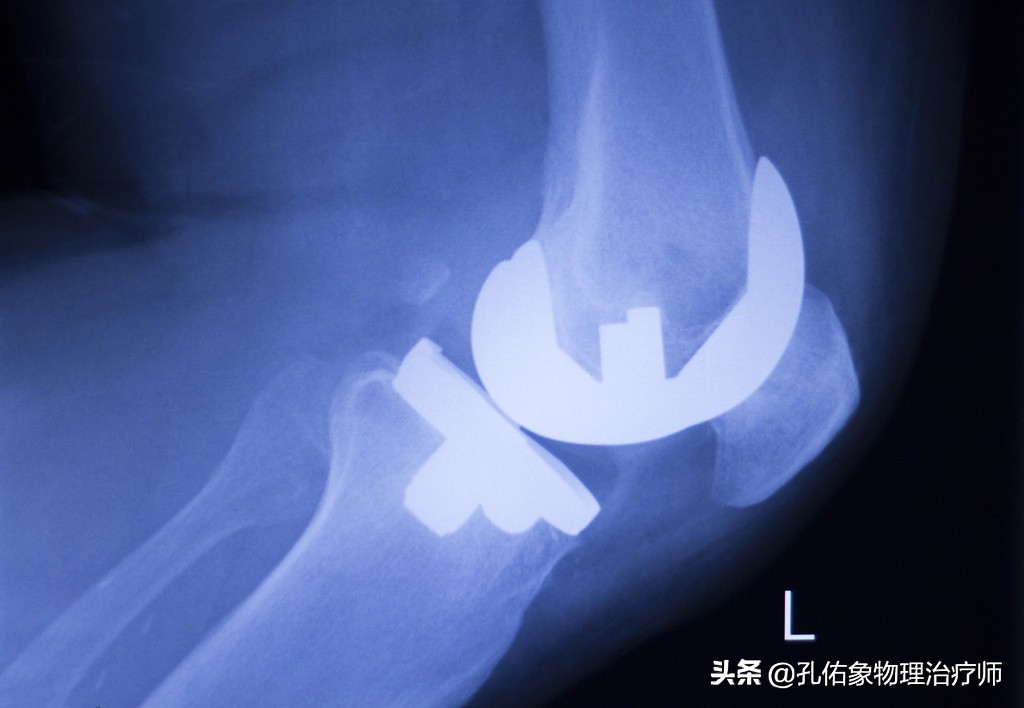

膝痛在早期时,往往只体现出局部的疼痛,局部的炎症肿胀;但是随着自身的不注意,慢慢的力学改变,膝盖骨与大腿骨撞击就会引起膝盖骨下面的软骨损伤,逐年累月的血液循环障碍、骨质增生、骨赘形成;到这个时候要解决问题,只有通过手术,关节镜下处理或是直接用一个假的膝关节换进去。

我们往往通过以上四个特殊检查就可以发现膝痛是不是膝盖骨的软骨软化所致?当然了,也可以去拍一张膝关节的正侧位片看看,一般早期疼痛往往在片子上也看不出啥问题,此时需要拍特殊体位的。

- 拍X片(轴位片)

一般在医院里边,很多医生也不会让患者去拍轴位片,都喜欢去拍正侧位片。但是对于膝痛早期的人而言,在下蹲过程中出现疼痛时的角度去拍轴位片,会发觉挺有意思的,膝盖骨是外移的,并没有在正常的髁间窝里边,这就是典型的膝盖骨软骨软化的表现。

这样的膝痛,在早期通过片子是很难发现的,所以你无论是做啥治疗,效果都不好。只有找到病因后,从根本的力学入手治疗才是上策。若是不及时治疗,使膝盖骨一直处于不正确的轨迹里面运动,最终膝痛厉害,活动受限,拍X正侧位片会显示膝盖骨边缘骨质增生、骨硬化改变及粗糙不平,膝盖骨关节间隙狭窄。